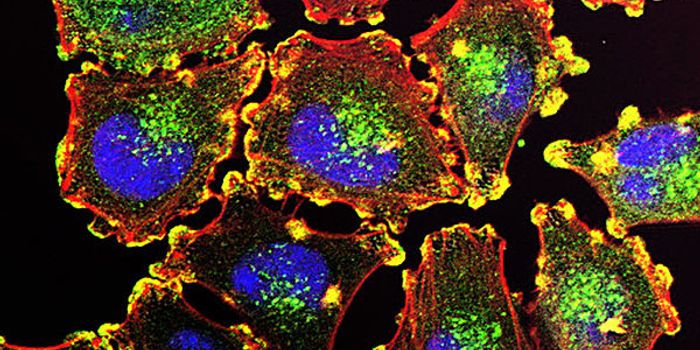

MAR 18, 2015Immunology

After a chance observation in the lab, researchers found a method that can force dangerous leukemia cells in the l ... -